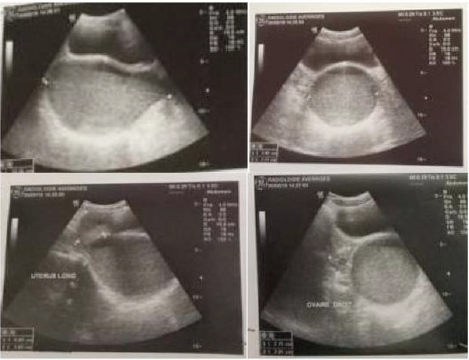

The clinical case is a 14 years old girl with a low social economic level, she had admitted to emergency for abdominopelvic pain, she had no medical history. there is no signs of urinary tract or digestive problems. General examination Find a conscious patient who is hemodynamically stable. Abdominal examination find A flexible abdomen with the presence of a right prlvic mass right which measerd about 10 cm in its large diameter without hepatosplenomegaly. Gynecological examination find A good development of the external genitalia, and secondary sex characteristics. An imperforate and bulging hymen, The rectal examination combined with the abdominal palpation reveals the existence of a soft, sensitive pelvic-abdominal mass varying in size from 8 to 12 cm. a pelvic ultrasound performed which revealed: A homogeneous uterus in the normal place measuring 6cm*4.7cm, with a regular outline. The intrauterine emptiness line is clearly visible, containing a hematometry slide. In the vaginal region: we note the presence of a voluminous oblong image, of thick content measuring 122*78*77mm.Both ovaries are normal in size, measuring 27*20mm at right and 22*15 on the left, and normal looking. The bladder is thin-walled alithiasis; The liver, spleen and both kidneys are free from abnormalities. The diagnosis of hematocolpos was confirmed and the patient undergone a surgical treatment under general anesthesia, the intervention consists of A Y-shaped incision at the hymen to avoid the urethra. The drainage brought back 550cc of blackish blood and the Placement of an intra-vaginal bladder catheter. The course was satisfactory, without stenosis. We dilated the orifice once a week for 1 month, then, once / 15 days, then once / month for 3 months. The patient was followed regularly for a year in consultation, then was lost to follow-up (Figures 1 & 2).

Figure 2: Suprapubic ultrasound: aspects in favor of a hematocolpos: oval collection of retrovesical fluid which communicates above with a normal size uterus.